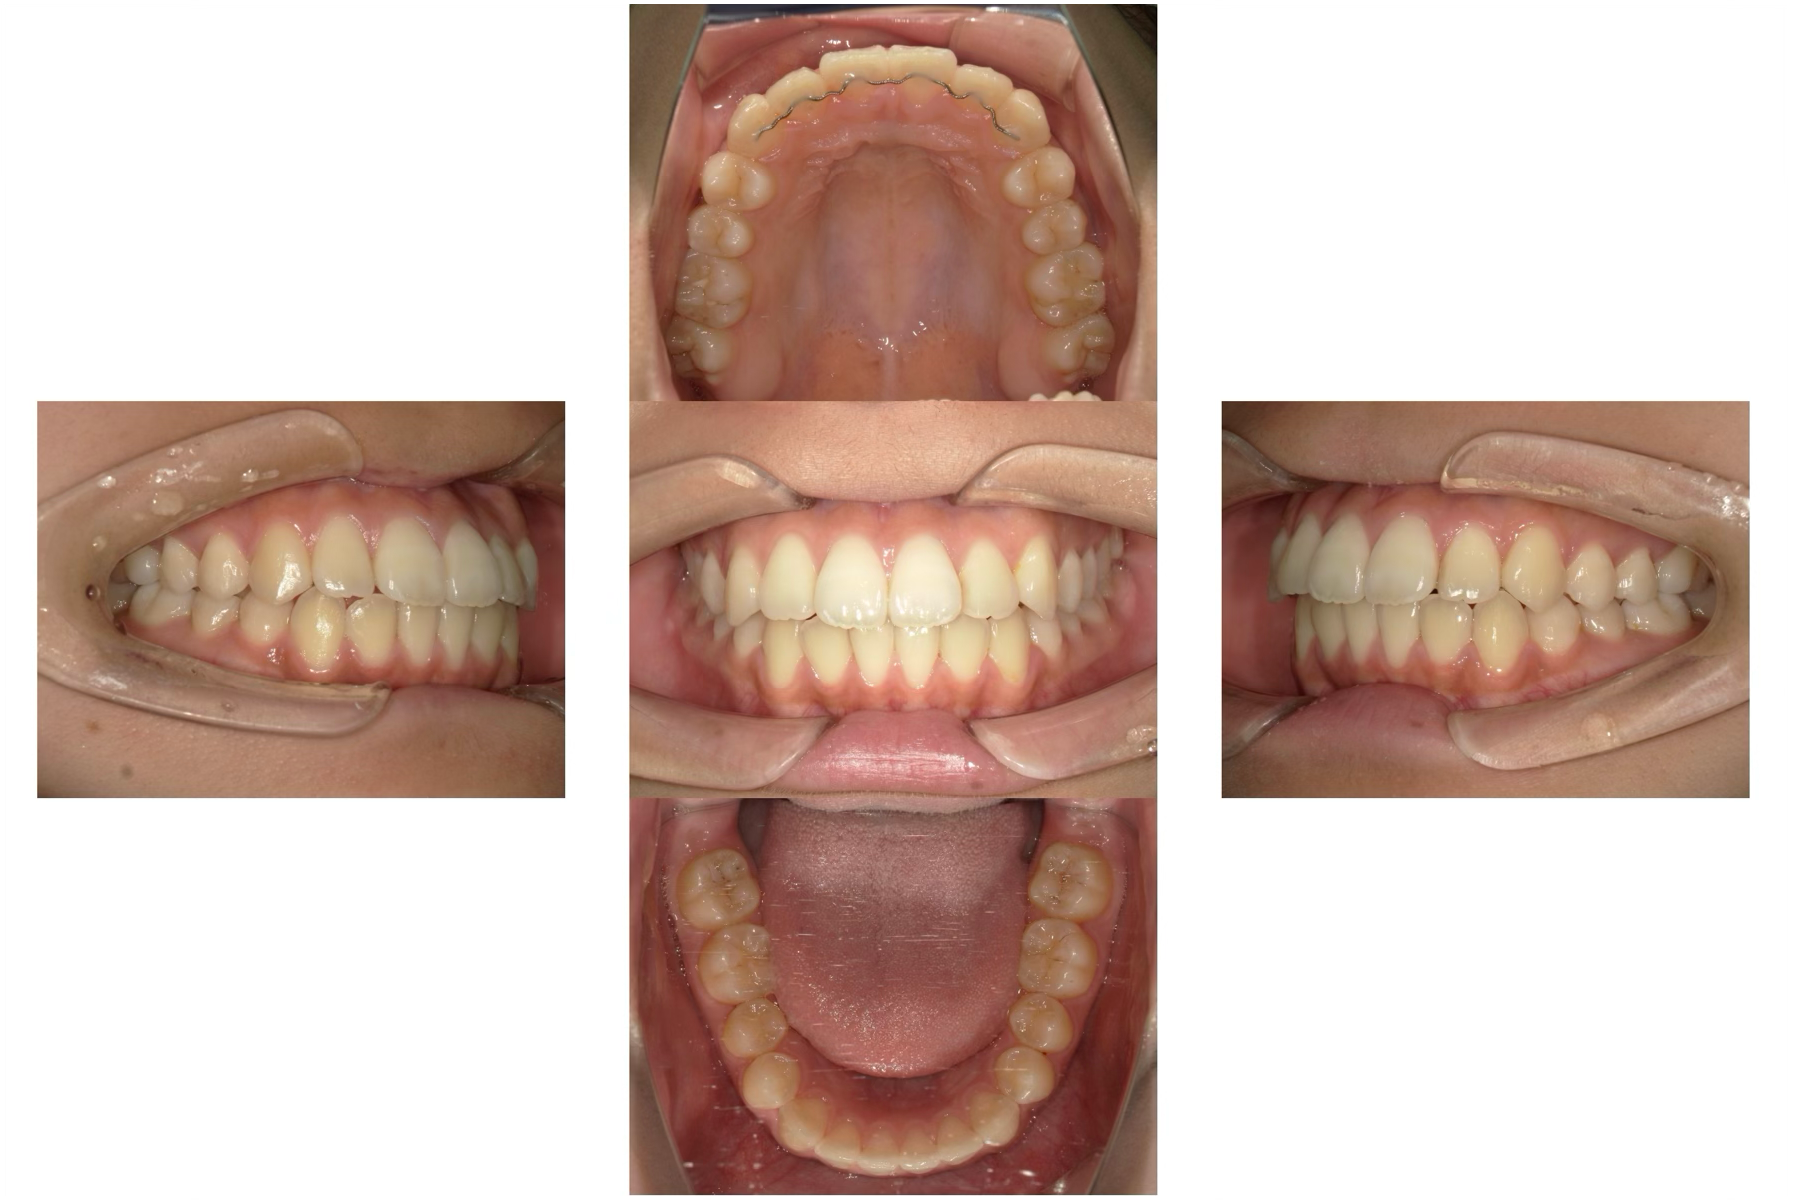

治療前

治療後

| 年齢 | 65歳 |

| 主訴 | 奥歯で硬いものが噛めない |

| 治療期間 | 約6ヶ月 |

| 治療費 | 約1,500,000円 |

| 概要 |

奥歯で固い食べ物が噛めず、年齢とともに噛み合わせや咀嚼機能の低下を実感されていました。 |